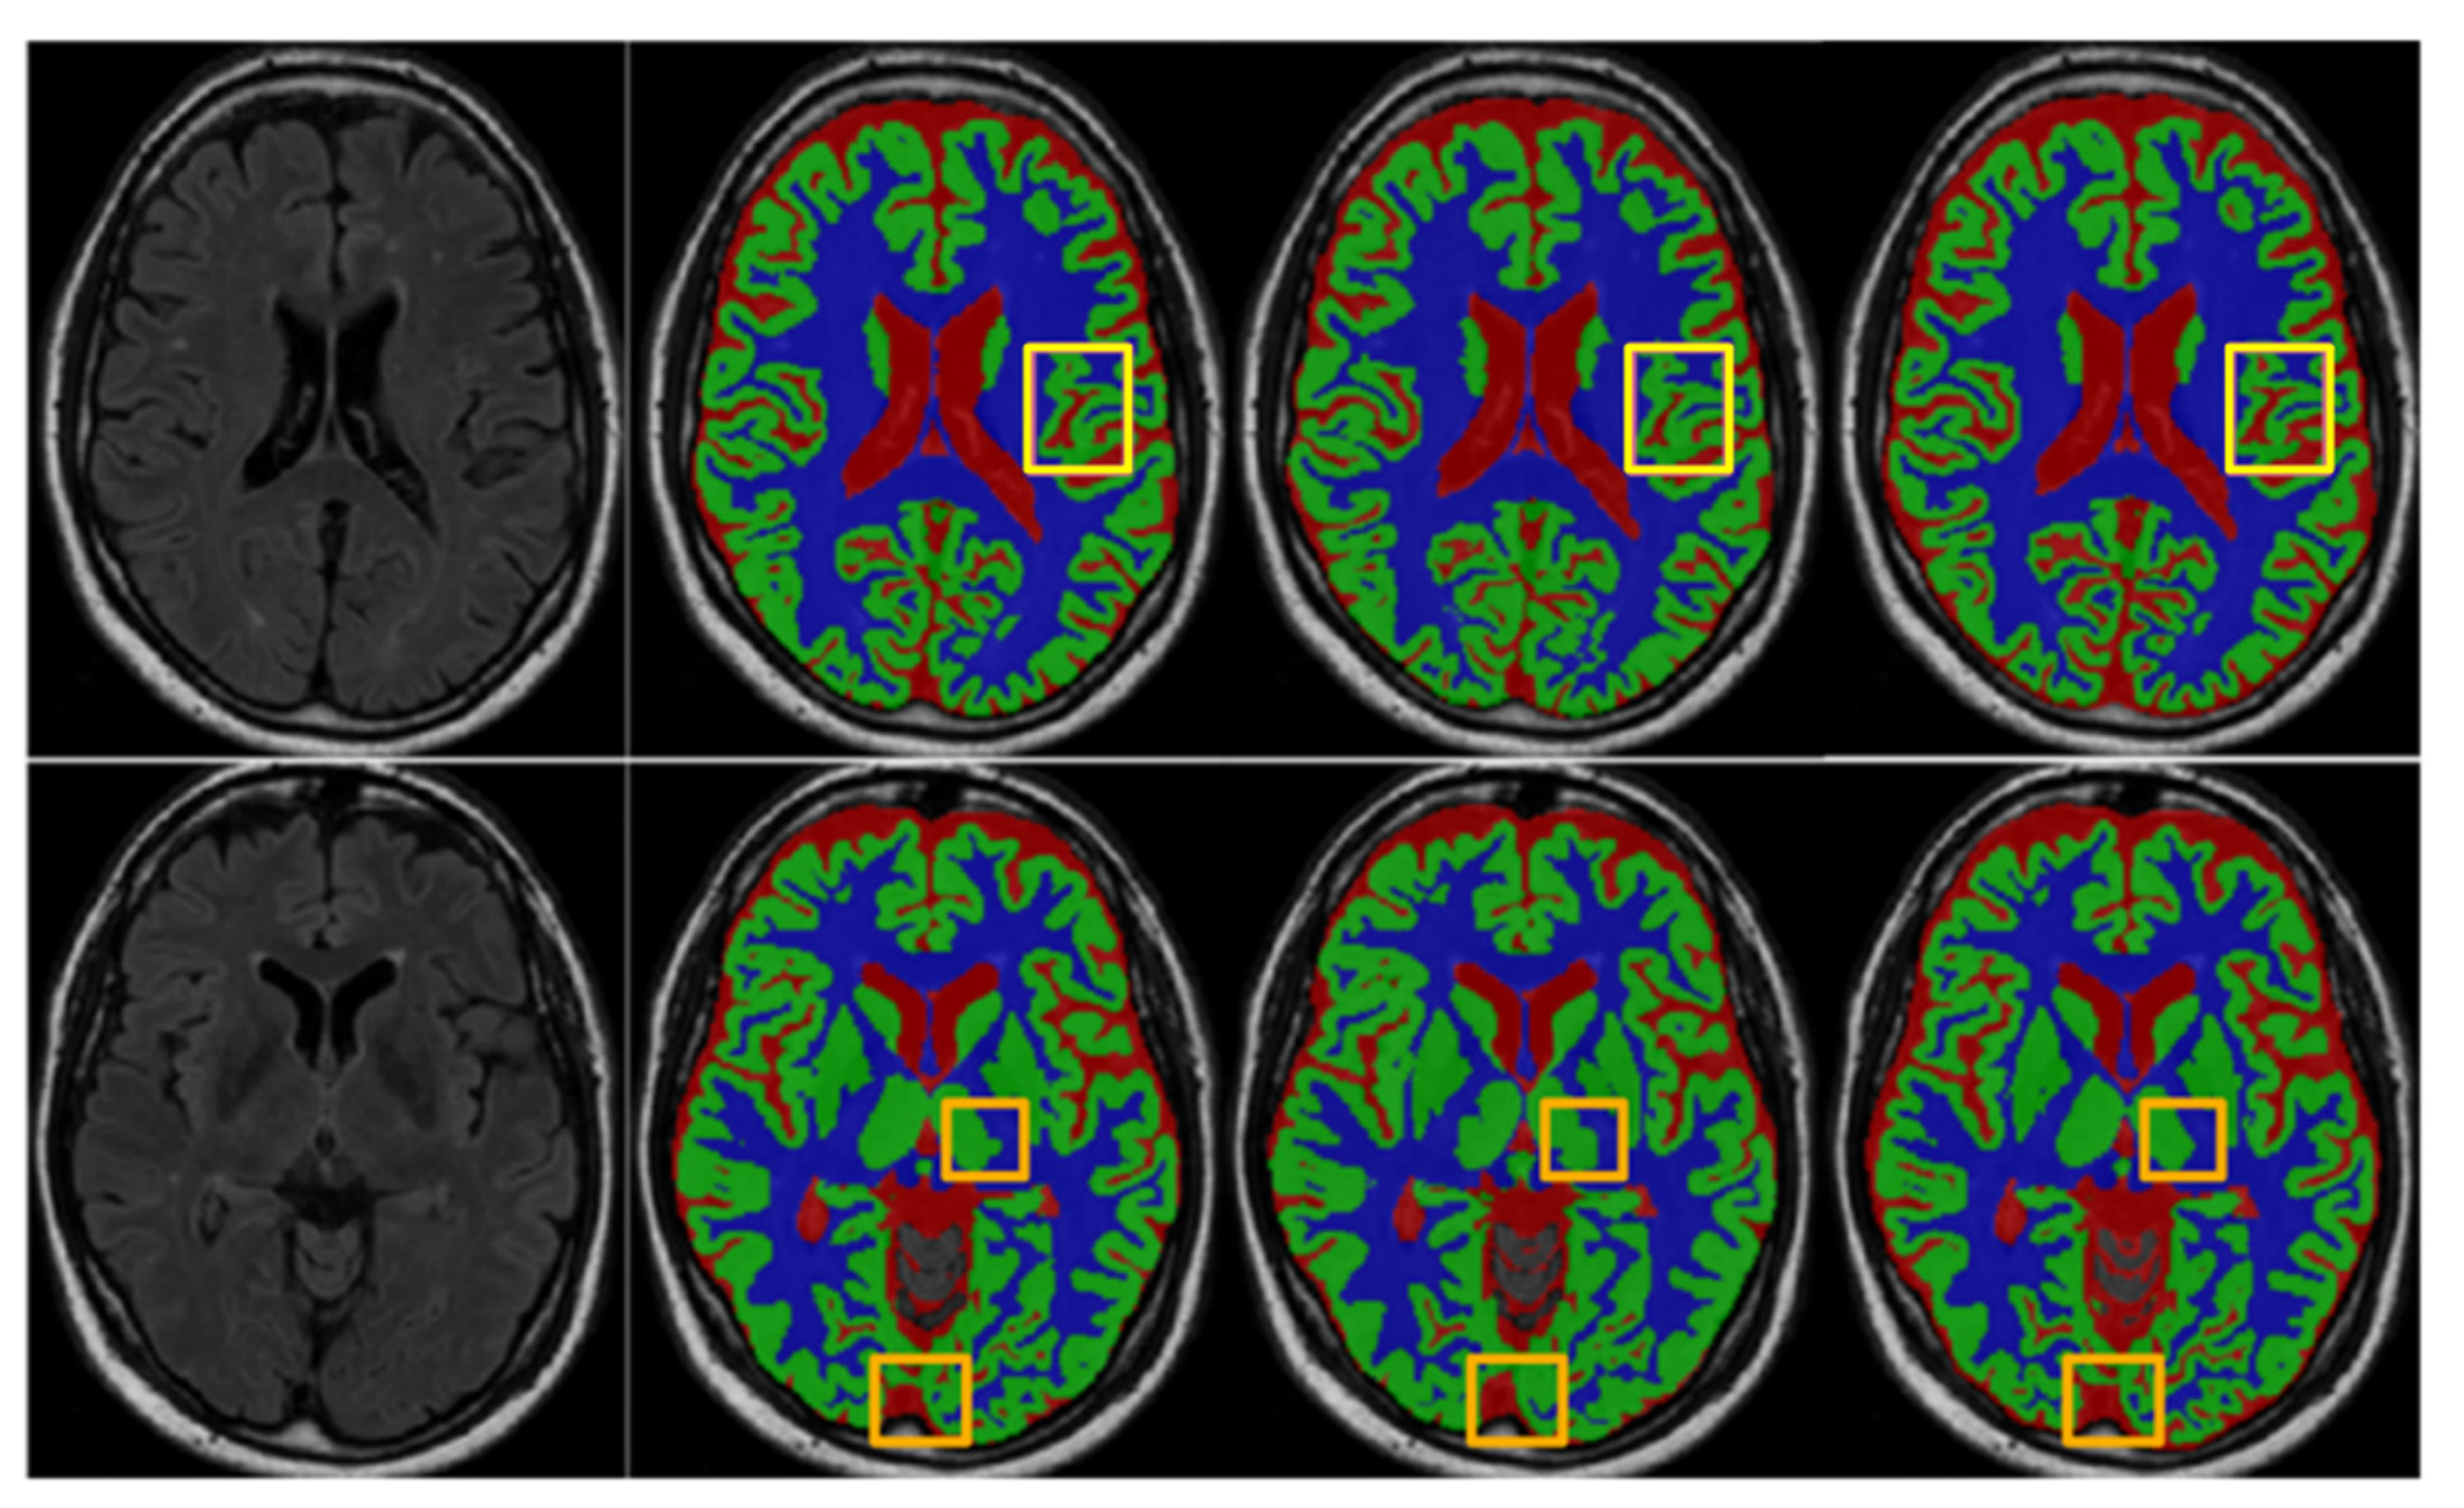

4. Results

4.3. Comparison with Existing State-of-the-Art Methods